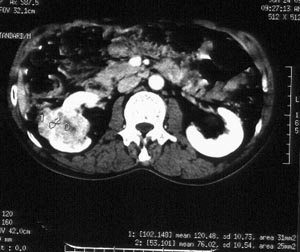

男性,56岁。右腰部不适2月。无血尿,无尿频尿急尿痛。b超提示:右肾下极占位。

ct平扫加增强扫描:右肾中下极肾盂外侧段实质见分叶状软组织密度肿块,截面大约56x45mm,向外突破肾包膜,向内突入肾盂,平扫密度略不均,ct值32-37hu。c+见病灶不均匀轻-中度强化,内有未强化坏死区。右侧肾周筋膜增厚,右肾内前方见肿大淋巴结。

ct诊断:右肾癌,ct表现见上述,伴同侧腹膜后淋巴结转移。